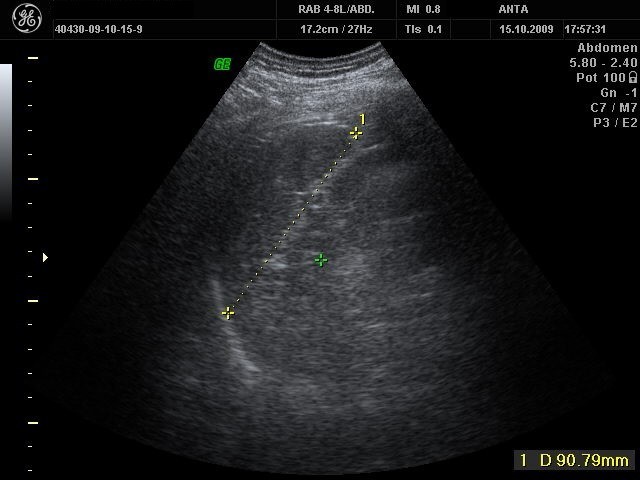

La ecografía o ecosonografía es un procedimiento de imagenología que emplea los ecos de una emisión de ultrasonidos dirigida sobre un cuerpo u objeto como fuente de datos para formar una imagen de los órganos o masas internas con fines de diagnóstico. Un pequeño instrumento «similar a un micrófono» llamado transductor emite ondas de ultrasonidos. Estas ondas sonoras de alta frecuencia se transmiten hacia el área del cuerpo bajo estudio, y se recibe su eco. El transductor recoge el eco de las ondas sonoras y una computadora convierte este eco en una imagen que aparece en la pantalla.